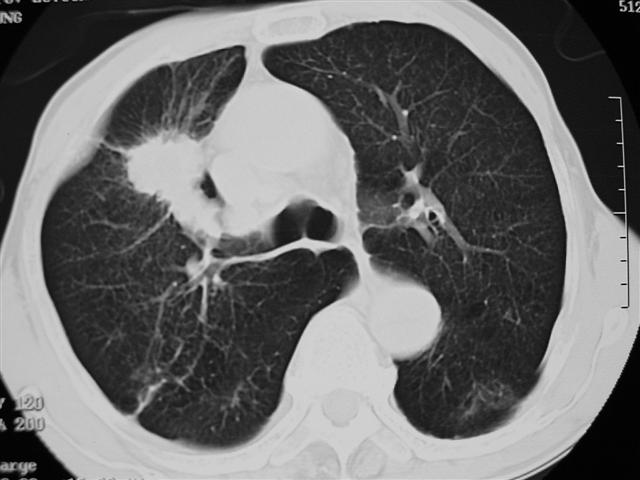

男,64岁,咳嗽、咳痰20余天,明显消瘦,x线片发现肺部阴影

长毛刺、肺门引流征象、中心液化坏死等应该是提示结核性肿块的可能性大,但是合并椎体及多处肋骨破坏则周围型肺ca并椎体及多处肋骨转移不能除外。

1)右肺上叶前段周围型肺癌并阻塞性肺炎、右肺门及纵隔淋巴结转移、肋骨及胸椎转移。2)右肺上叶后段纤维病灶。